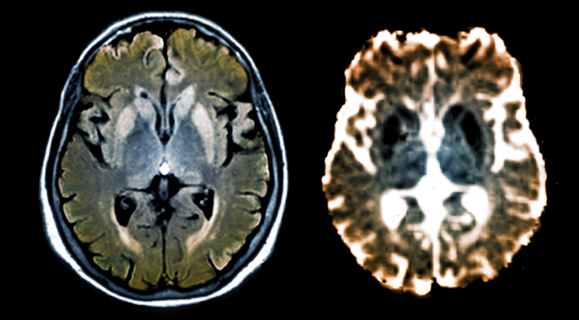

מחלות מורכבות יותר ממה שחשבנו. סריקות מוח של חולה במחלת הפריונים קרויצפלד-יעקב | מקור: Science Photo Library